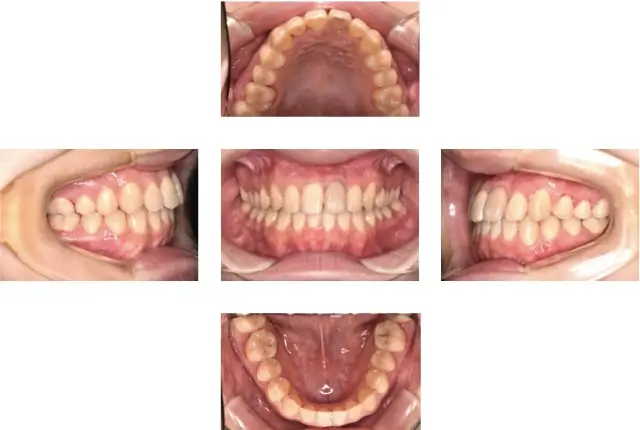

受け口(下顎前突)治療 2

初診時年齢 11歳10ヶ月 主訴 でこぼこと受け口が気になる

診断名 叢生を伴う下顎前突 治療に用いた主な装置 マルチブラケット装置

抜歯の有無 抜歯(上下顎左右側4番抜歯) 治療期間/回数 2年6ヶ月/25回

費用の総額 1,072,500円(税込) 費用内訳

初診時年齢 11歳10ヶ月

主訴 でこぼこと受け口が気になる

診断名 叢生を伴う下顎前突

治療に用いた主な装置 マルチブラケット装置

抜歯の有無 抜歯(上下顎左右側4番抜歯)

治療期間/回数 2年6ヶ月/25回

費用の総額 1,072,500円(税込)